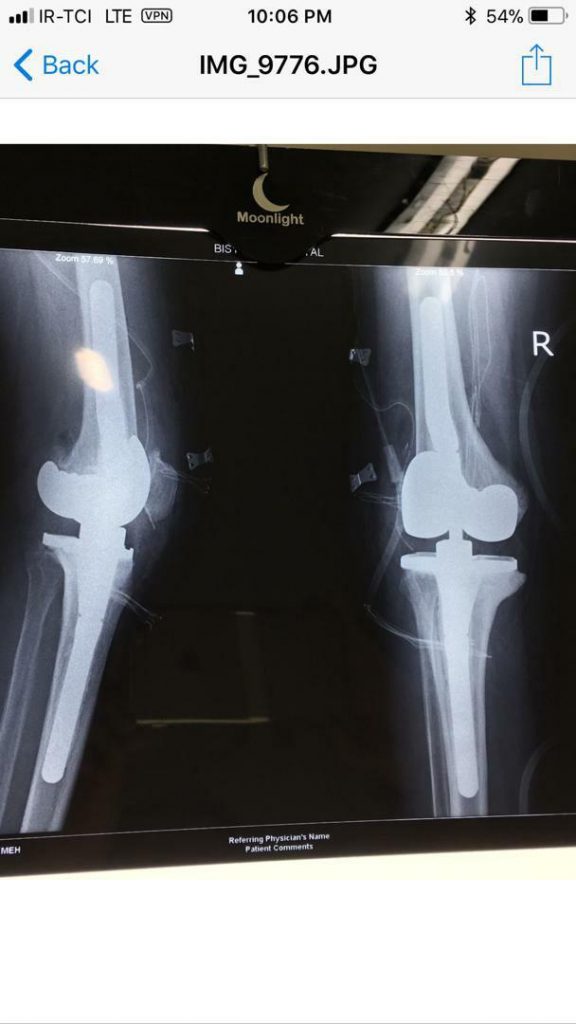

جراحی تعویض مفصل چیست؟

درصورتی که شدت آسیب وارد شده به مفصل به گونه‌ای باشد که با سایر روش‌های درمانی آسیب برطرف نشود، جراح ارتوپد عمل تعویض مفصل را برای درمان توصیه می‌کند. با این عمل، بخشی یا همه محل آسیب دیده مفصل با پروتز جایگزین می‌شود. عمل تعویض مفصل به طرز قابل توجهی درد مفاصل آسیب دیده را کاهش می‌دهد، موجب بهبود توانایی حرکتی مفصل و کاهش مشکلات حرکتی فرد و به طور کلی باعث بهبود کیفیت زندگی فرد می‌شود.

انواع عمل جراحی‌ تعویض مفصل یا آرتروپلاستی، با توجه به نوع مفصل عبارتند از: عمل تعویض مفصل زانو، عمل تعویض مفصل لگن و ران، عمل تعویض مفصل شانه، عمل تعویض مفصل آرنج و عمل تعویض مفصل مچ پا.